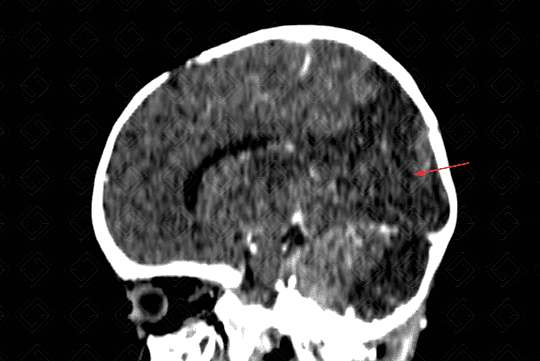

Texto alternativo para a imagem Figura 3. Créditos: Dra. Elazir Mota - Rio de Janeiro/RJ

Descrição da lesão: Acidente vascular encefálico isquêmico (AVE).

Descrição das figuras 1, 2 e 3: Tomografia computadorizada do crânio após a administração do contraste evidenciando extensa hipodensidade nas regiões parietal e occipital esquerdas com extensão ao tálamo deste lado (visualizado na reconstrução sagital), sem causar efeito compressivo, compatível com evento isquêmico subagudo (setas vermelhas).

Por volta de 24 a 72 horas, de fato, surge a hipodensidade do território vascular acometido (figuras 1, 2 e 3).